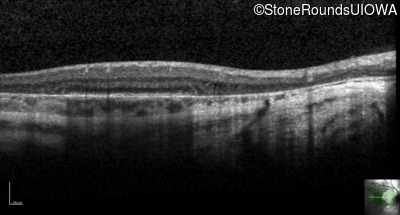

Age at visit: 36 years